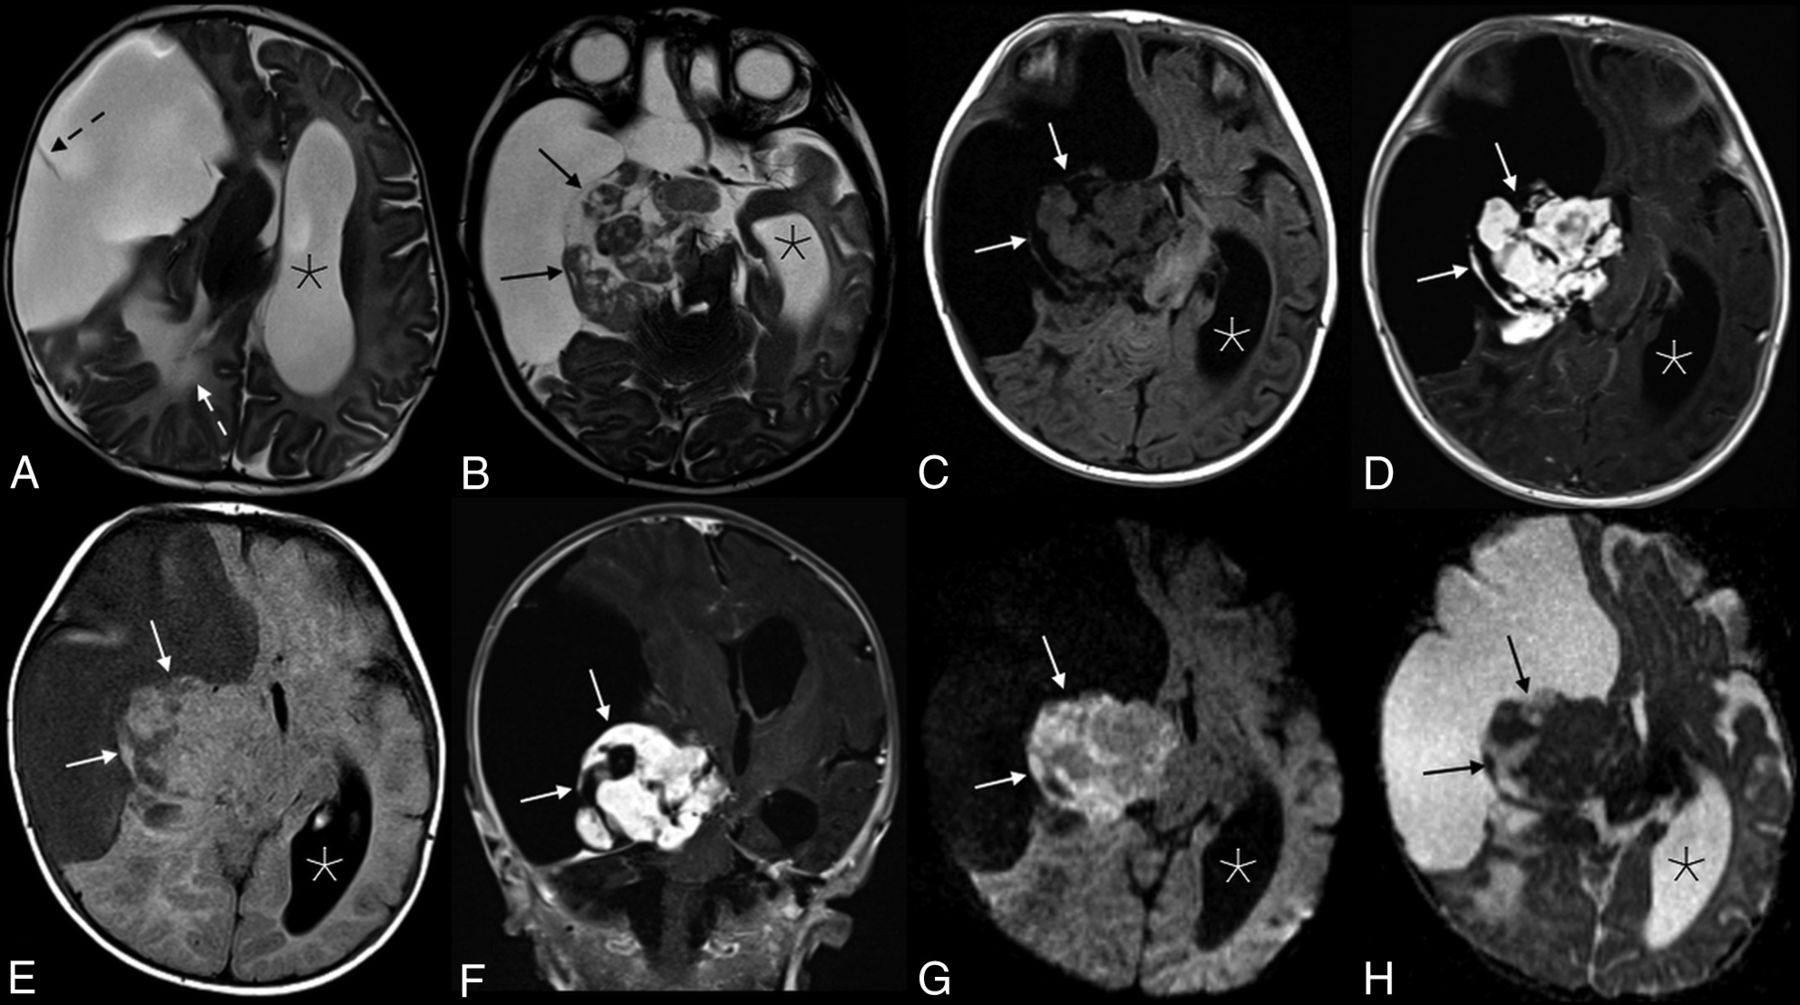

MR imaging showed a massive lesion in the right cerebral hemisphere with both cystic and solid components (Fig 1). The cystic aspects made up most of the mass and had a thin internal septation. The lobulated solid components were located centrally near the brain stem and were T2 isointense and heterogeneous with avid enhancement. Associated mass effect was present, including a leftward midline shift, right lateral ventricular effacement, and right basal ganglia and brain stem compression. Confluent T2 hyperintensity within the parenchyma posterior to the mass represented edema and/or gliosis. The cerebral aqueduct was compressed, causing left lateral and third ventricular dilation, though with minimal periventricular edema.

Appearance of the solid tumor component on various sequences. Axial T2 (A and B), axial T2 FLAIR (C), and T1 FLAIR (D) images showed a predominantly cystic mass in the right cerebral hemisphere with a heterogeneous solid component (black arrows in B, and H; white arrows in C–G) along the medial aspect of the tumor margin. A single thin septation was present within the cystic component (dashed black arrow, A). There is significant associated mass effect with T2 hyperintensity in the adjacent right parietal lobe white matter (white dashed arrow, A), a leftward midline shift, and compression of the right basal ganglia, brain stem, and right cerebral and middle cerebellar peduncles. The left lateral ventricle (asterisks) and third ventricle (not shown) were obstructed, causing marked ventricular dilation. Avid enhancement of the solid component is demonstrated in the axial (D) and coronal (E) T1WI + Gadolinium images. Heterogeneous mild intralesional restricted diffusion (G and H) is atypical for these tumors.

The cystic component of the mass appeared to be extra-axial, evidenced by buckling and compression of the adjacent normal cortex. However, the solid components appeared to be at least partially intra-axial, with complete absence of normal temporal lobe parenchyma.

A massive, predominately cystic supratentorial mass presenting in an infant was suggestive of a desmoplastic infantile tumor (DIT), which includes both desmoplastic infantile gangliogliomas (DIGs) and astrocytomas (DIAs). However, mild-to-moderate restricted diffusion was seen within the solid components of the lesion, which would be atypical for this tumor (Fig 1). An infantile glioblastoma was also considered, given the shared imaging characteristics of both tumors and intralesional restricted diffusion. Other diagnostic considerations were thought to be less likely, including an embryonal tumor with multilayered rosettes, atypical teratoid/rhabdoid tumor, supratentorial ependymoma, and pleomorphic xanthoastryocytoma.